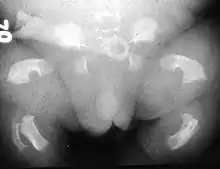

Radiogram of a baby born with thanatophoric dwarfism | |

Thanatophoric dysplasia is a severe skeletal disorder characterized by a disproportionately small ribcage, extremely short limbs and folds of extra skin on the arms and legs.

Infants with this condition have disproportionately short arms and legs with extra folds of skin. Other signs of the disorder include a narrow chest, small ribs, underdeveloped lungs, and an enlarged head with a large forehead and prominent, wide-spaced eyes. Thanatophoric dysplasia is a lethal skeletal dysplasia divided into two subtypes. Type I is characterized by extreme rhizomelia, bowed long bones, narrow thorax, a relatively large head, normal trunk length and absent cloverleaf skull. The spine shows platyspondyly, the cranium has a short base, and, frequently, the foramen magnum is decreased in size. The forehead is prominent, and hypertelorism and a saddle nose may be present. Hands and feet are normal, but fingers are short. Type II is characterized by short, straight long bones and cloverleaf skull.[1] It presents with typical telephone-handle shaped long bones and H-shaped vertebrae.

Infants with type 1 thanatophoric dysplasia also have curved thigh bones, flattened bones of the spine (platyspondyly) and shortened thoracic ribs. Note: Prenatal ultra-sound images of the ribs sometimes appear asymmetrical when in fact they are not. In certain cases, this has caused a misdiagnosis of osteogenisis imperfecta (OI) type II.